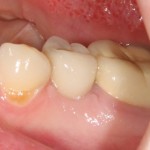

Немедленная имплантация — оптимальное решение в любой клинической ситуации